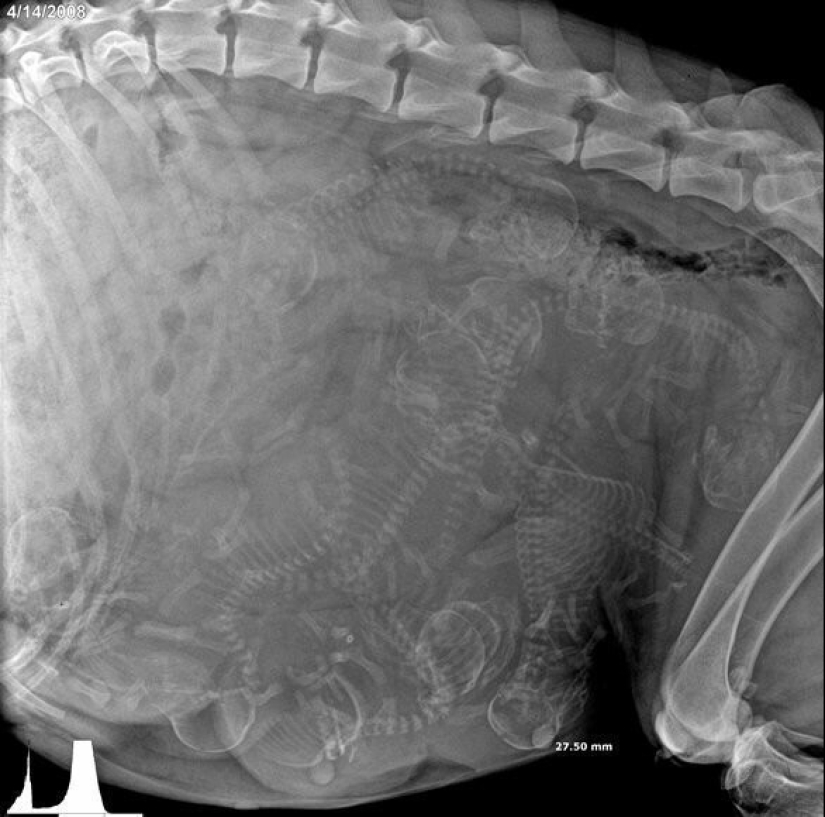

Quién vive en la casita: radiografías de animales preñados

Por Pictolic https://pictolic.com/es/article/quien-vive-en-la-casita-radiografas-de-animales-prenados.html¿Alguna vez te has preguntado qué sucede en el útero de una gata o una perra preñada? ¿Cómo encajan todos estos pequeños bebés allí y logran desarrollarse durante todo el embarazo? La mayoría de los animales preñados se examinan mediante rayos X. Y éstas, cabe señalar, son fotografías muy interesantes.

Especialistas que como parte de su trabajo observan animales que están listos para parir, compartieron estas sorprendentes imágenes de rayos X y ultrasonido.

Conejillo de Indias embarazada